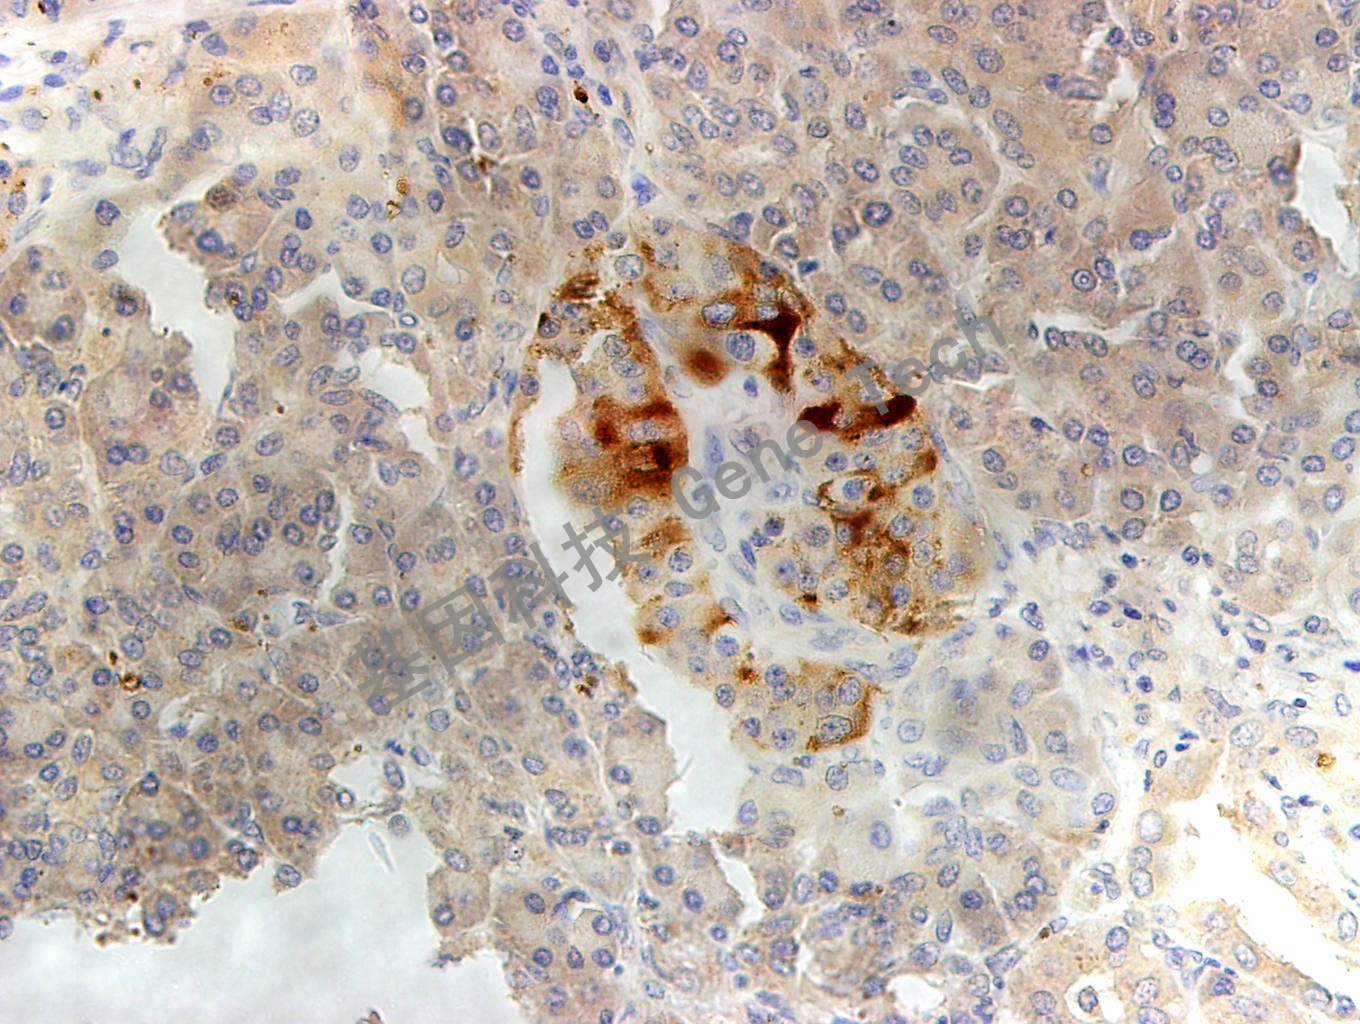

MMP-2 鼠抗人 基質(zhì)金屬蛋白酶 2

| 克隆號:4D3 | 種屬:鼠 | 適用染色系統(tǒng):GTvisionTM |

| 預(yù)處理:高pH熱修復(fù) | 陽性部位:細胞漿 | 陽性對照:胰腺癌 |

| 簡介:MMP-2(Matrix metallopeptidase 2)又名IV型膠原酶,能夠降解IV、V、VII、X 型膠原和I型明膠。MMP-2的活化由Ras信號途徑介導(dǎo)。 | ||

| 胰腺癌石蠟切片,用 MMP-2(GT2265)染色,細胞漿陽性,DAB 顯色。 | ||